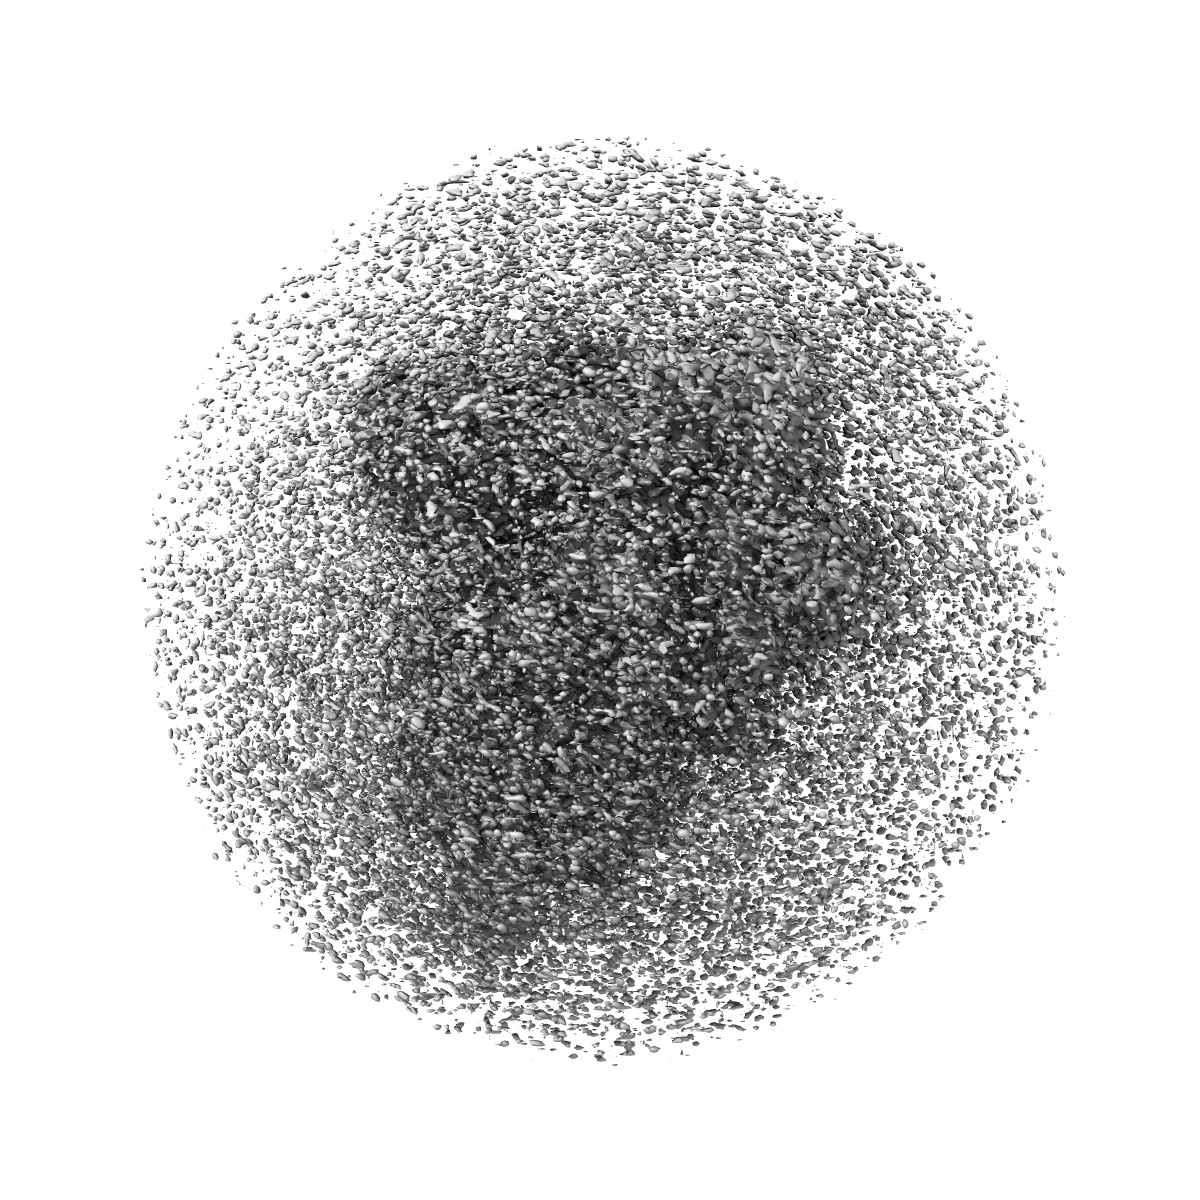

Structure of the SARS-CoV-2 spike glycoprotein in complex with a human single domain antibody n3113 (UDD-state, state 1)

Single-particle3.7 Å

Sample: Complex of SARS-CoV-2 spike with n3113